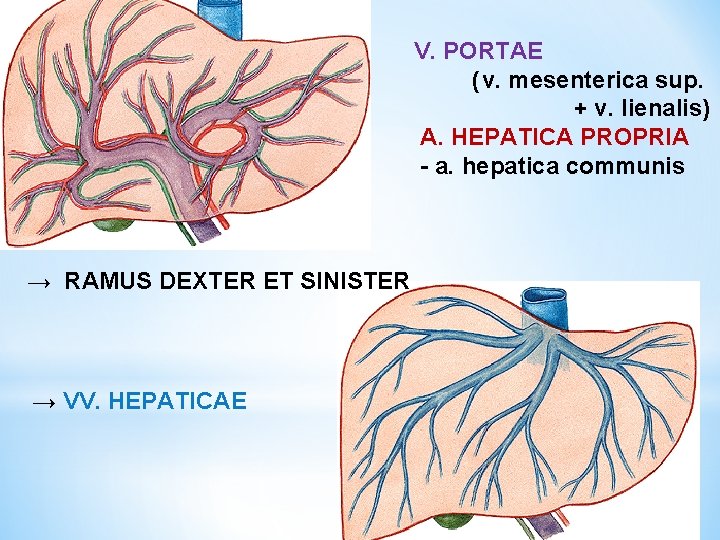

V. PORTAE (v. mesenterica sup. + v. lienalis) A. HEPATICA PROPRIA - a. hepatica communis → RAMUS DEXTER ET SINISTER → VV. HEPATICAE